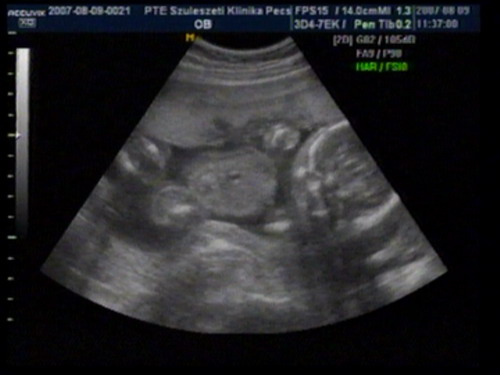

szedtünk le a videoról képet: Kép